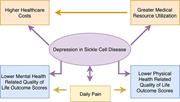

Depression, quality of life, and medical resource utilization in sickle cell disease

Depression, quality of life, and medical resource utilization in sickle cell disease